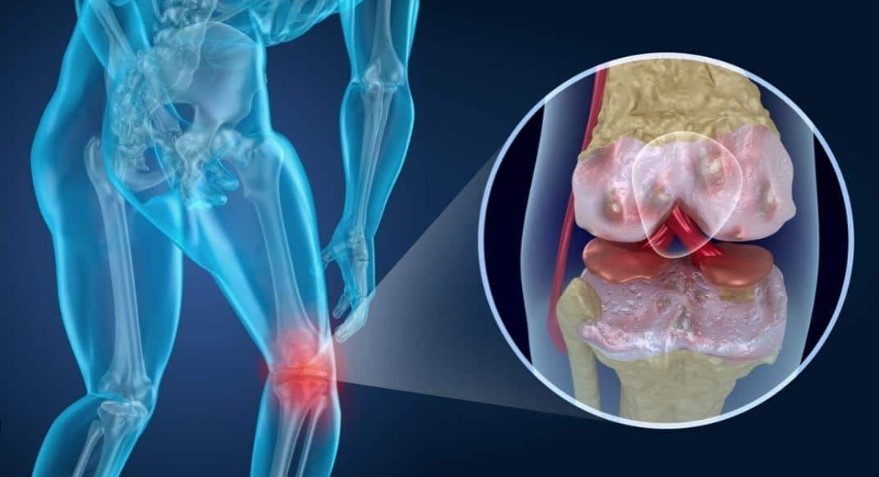

Kıkırdak aşınmalarını gideriyor

Kıkırdak aşınmalarını gideriyor

Kıkırdak aşınmalarını gideriyor! Yoğurtun kaşık kaşık içerisine eklenmesi: Kemiklere kalsiyum işleniyor, diz ağrılarını sıfırlıyor. Son yıllarda halk arasında oldukça popüler hale gelen yoğurt ve çörek otu karışımı, yöntemlerle da önerilen doğal desteklerden biri. Bu ikili hem güçlü bir antioksidan etki gösteriyor hem de besin değerleri sayesinde kıkırdak ve kemik yapısının korunmasına katkıda bulunuyor. Tarifi ve Detaylı Açıklayıcı Bilgileri..